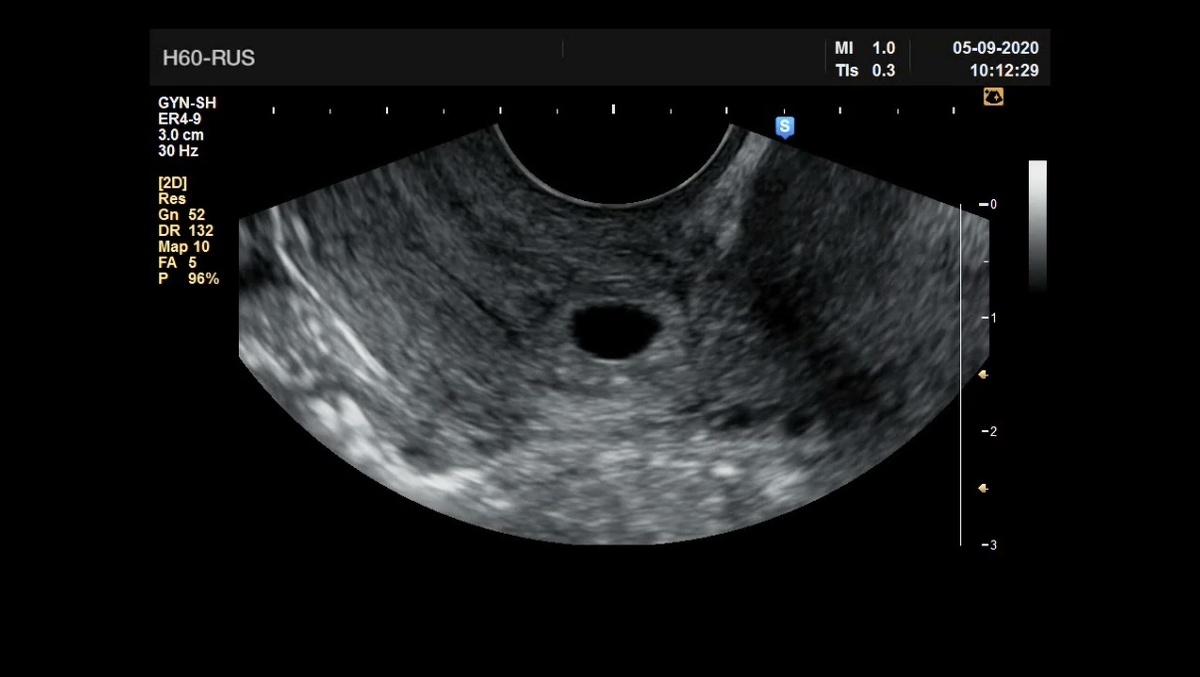

Шеечная беременность малого срока. Фото из телеграм-канала для специалистов УЗД